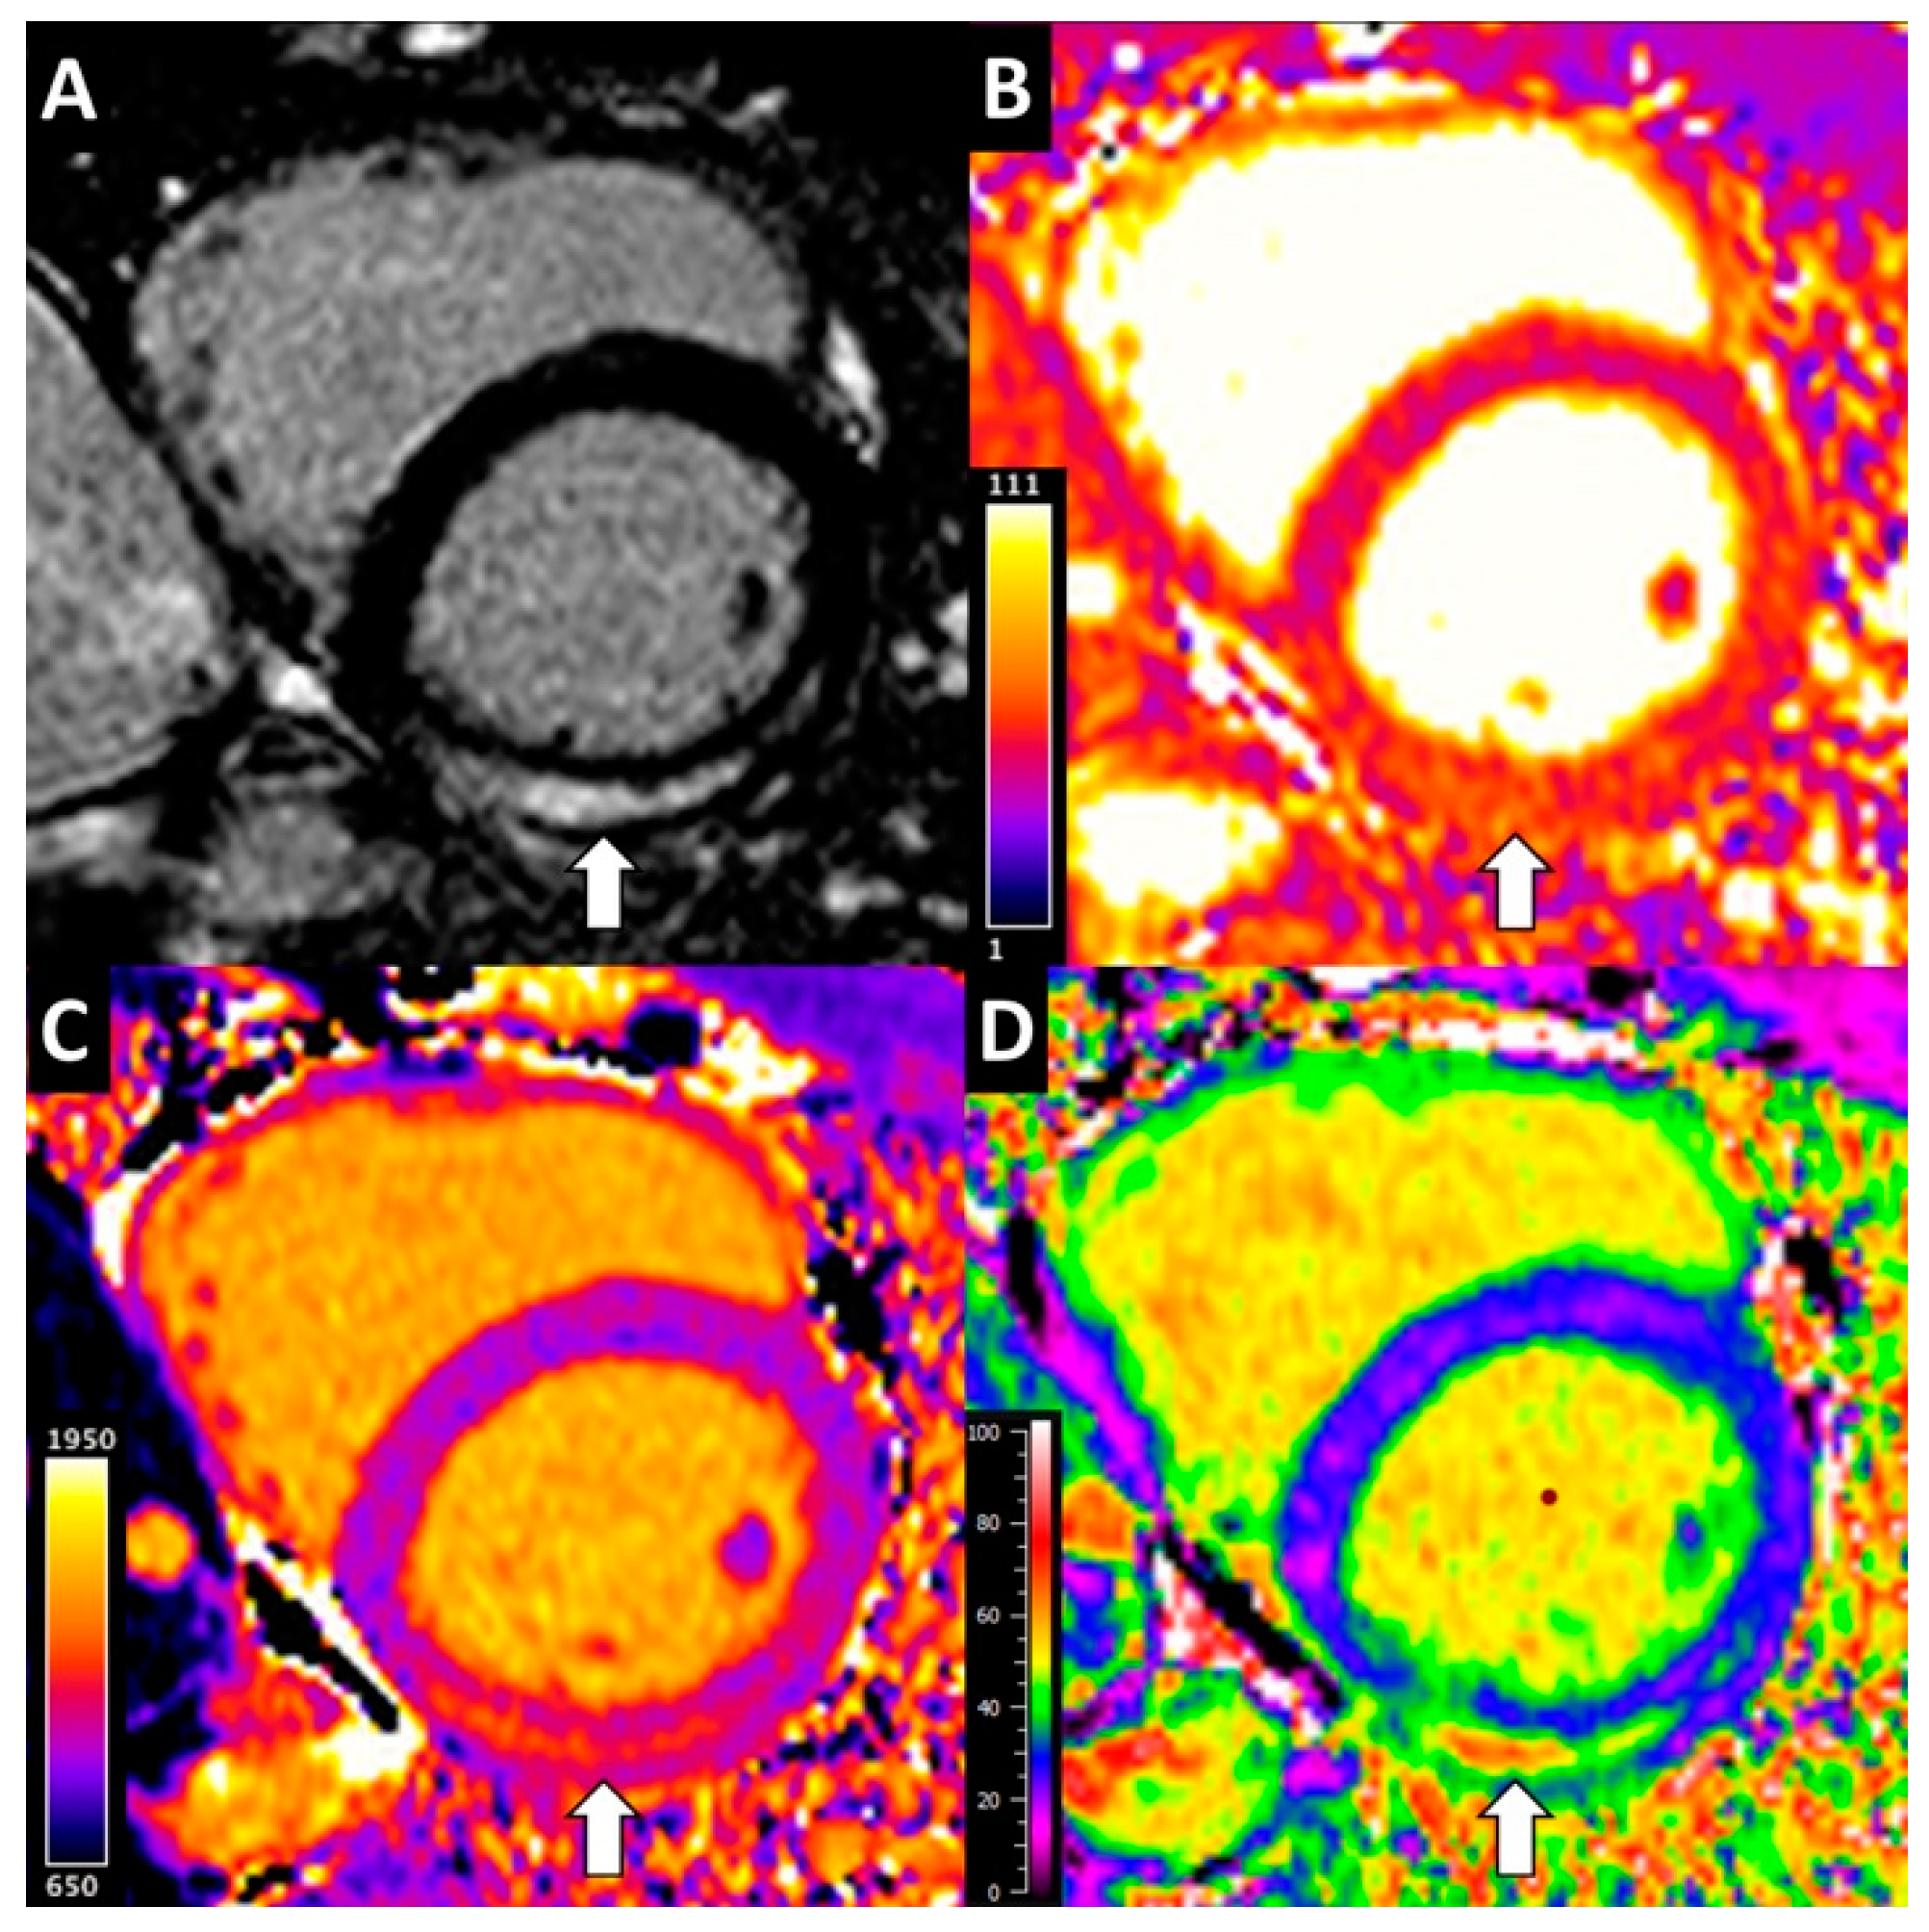

2.3. CMR Analysis